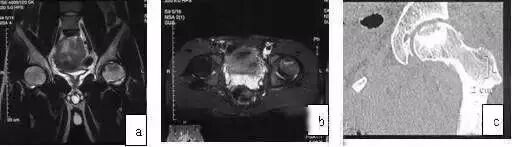

发生在髋关节的PVNS较膝关节少得多,患者多为青少年,常为单发,髋部中、轻度疼痛伴明显关节功能障碍,X线摄片可见股骨头、颈及髋臼皮质骨侵袭,囊性变,关节间隙变窄,此与ONFH不同,后者早、中期时关节间隙不变窄。

应用MRI检查,则鉴别不难。MRI示广泛滑膜病变(T1WI、T2WI均为低信号),病变侵犯广泛(股骨头颈、髋臼)是其特点,CT扫描可见骨皮质侵蚀,累及髋臼和股骨头、颈部,与ONFH鉴别不难(图10)。

图10 男,28岁,右髋钝痛二年,关节活动明显受限,诊断为色素沉着绒毛结节滑膜炎。(a)MRI的T1WI示右股骨头、颈弥散性低信号;(b)X线片示右髋股骨头及髋臼破坏,关节间隙变窄;(c)CT扫描示股骨头颈骨破坏